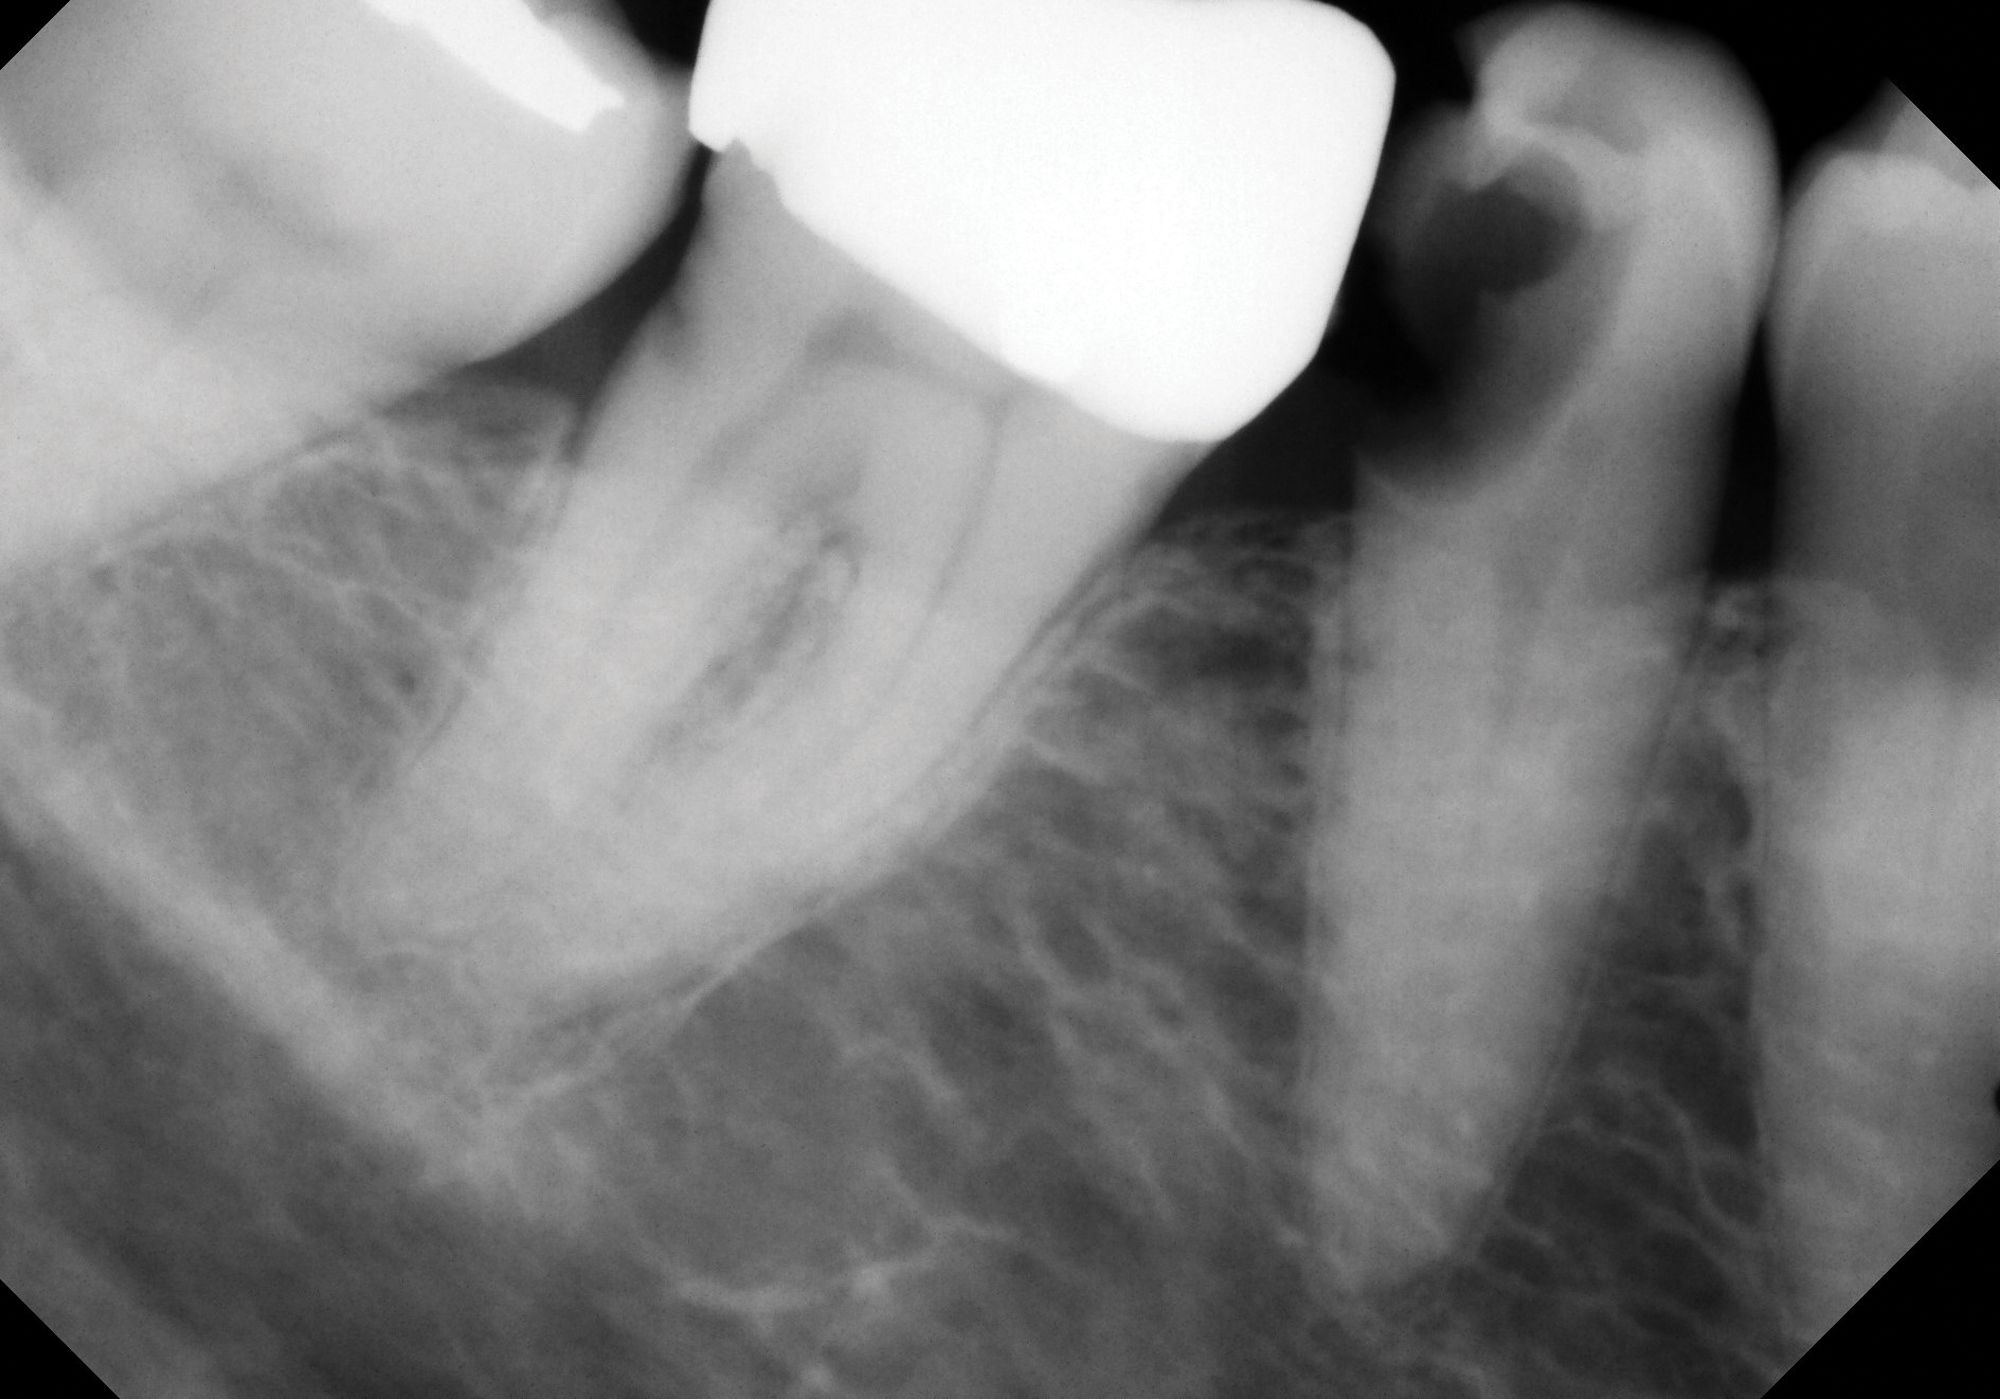

Figure 3A.

Figure 3B. Although vital pulp therapy was planned for tooth No. 31 during the consultation visit—at which the patient had no symptoms or abnormalities on clinical testing (A) —discomfort and cold sensitivity on the day of treatment were consistent with hyperemic pulp tissue extending into the roots. The diagnosis of symptomatic irreversible pulpitis instead warranted nonsurgical root canal therapy to manage (B)